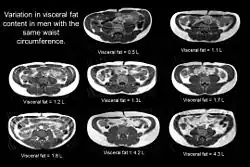

To classify an individual as TOFI, it is essential to measure their internal fat content. This is done by using magnetic resonance Imaging (MRI) or CT scanning. The parameters of the MRI scanner are manipulated to show fat as bright (white) and lean tissue as dark.

Indirect methods such as waist circumference are not suitable as individuals with an identical waist circumference can have vastly different levels of internal fat.

The figure clearly shows that despite having an identical waist circumference (in this example all men had a waist of 84 cm), there is considerable variation in the amount of visceral fat (volumes shown on the image in litres) present.